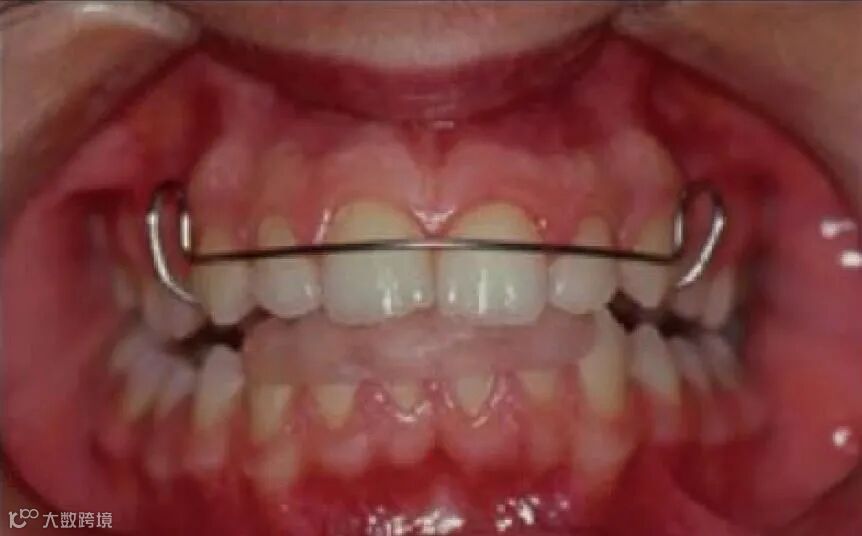

使下颌处于前伸位置,使相关的肌肉做出反应,从而获得纠正牙齿、牙弓关系所需的正畸力,而最终目标是改善患者面貌,见图1~图2。

图2 肌激动器口内正面像